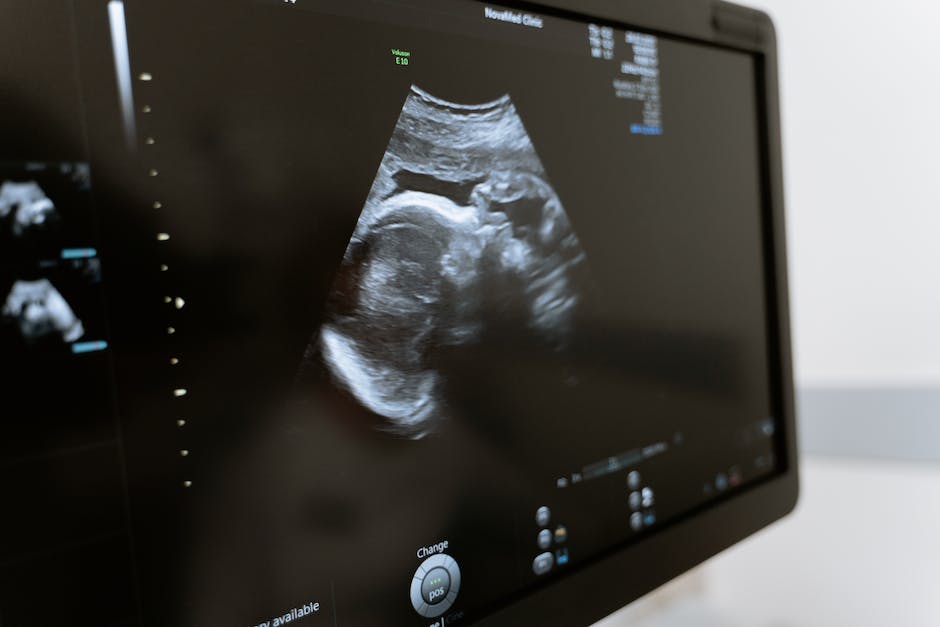

분당산부인과에서는 수술이 일반적으로 난소낭종의 치료 방법입니다. 난소낭종이 크거나 증상이 심한 경우 수술이 필수적입니다. 난소낭종 수술은 초음파 검사를 통해 난소낭종의 크기와 위치를 확인하고, 이를 기반으로 소총을 이용한 경피적 접근법이 주로 사용됩니다. 이 방법은 작은 절개를 통해 난소를 수술하는데, 수술 부위의 손상을 최소화하여 빠른 회복을 돕고, 흉터 역시 작게 남게 합니다.